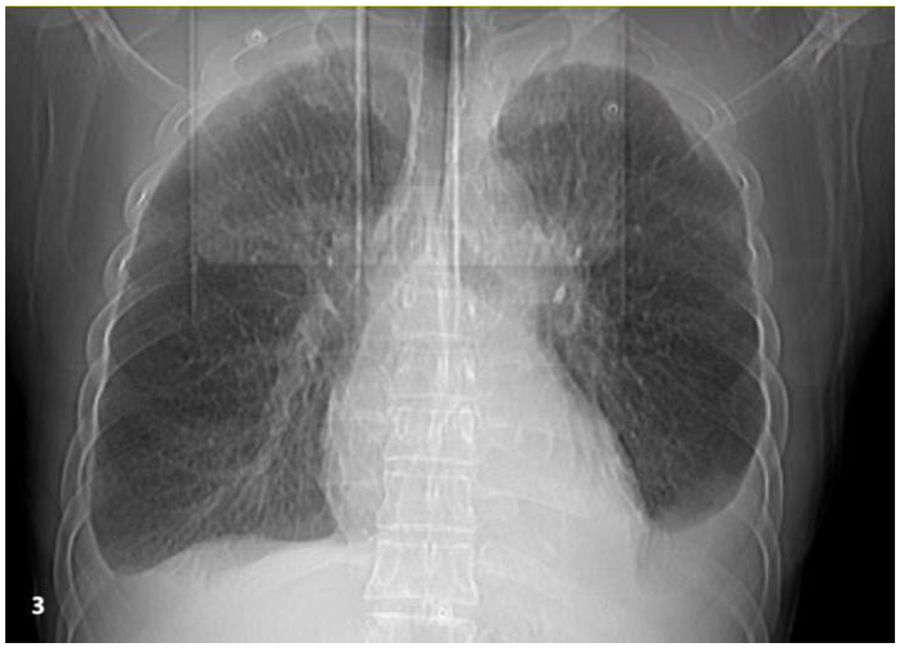

The patient is a 50-year-old male who was admitted to the hospital on March 28, 2022, due to “chest tightness and dyspnea for 3 weeks after physical activity.” Physical examination revealed BP: 100/60 mmHg, HR: 150 beats per min, with an absolutely irregular heart rhythm, and oxygen saturation of 100%. The cardiac dullness border was enlarged; no jugular venous distension was observed, and pitting edema was present in both lower limbs. Muscle strength in all four limbs was normal.An electrocardiogram (ECG) (Figure 1) showed rapid atrial fibrillation with low voltage in limb leads. Echocardiography (Figure 2) suggested a primary consideration of cardiac amyloidosis: enlarged left atrium, symmetrical thickening of the left ventricular myocardium, dense and enhanced myocardial echoes with granular sparkling strong echoes, thickened right ventricular wall (free wall thickness 0.74 cm), preserved apical strain in the left ventricle presenting a “cherry on top” sign (LV GLS = −6.2%), thickened mitral and tricuspid valves with mild regurgitation, reduced left ventricular systolic function (EF: 47.8%), decreased left ventricular diastolic function (grade 3), and a small amount of pericardial effusion. The aortic valve had a congenital bicuspid malformation (Type 1), with currently acceptable valve function. Chest CT revealed moderate pleural effusion bilaterally with adjacent lung tissue atelectasis (Figure 3). Blood tests showed NT-proBNP: 5,150 pg/mL (normal: <125 pg/mL below75 years old), BNP: 650.4 pg/mL (normal: <100 pg/mL), LDH: 253 U/L (normal: 125–220 U/L), CK: 73 U/L (normal:38–174 U/L), CK-MB: 20 U/L (normal: <5–25 U/L), cTnI: 0.048 ng/mL (normal: <0.04 ng/mL).

Figure 3

Chest imaging reveals bilateral moderate pleural effusions with atelectasis of the adjacent lung tissue caused by the pleural effusion.